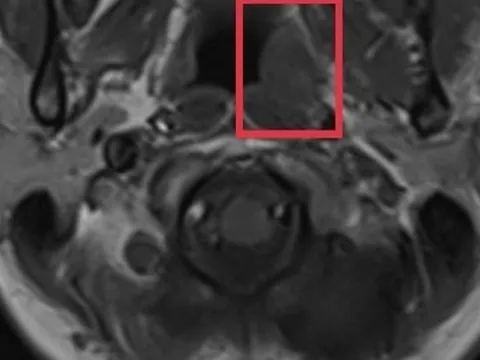

Cẩn trọng với loại ung thư nguy hiểm nhưng có triệu chứng mơ hồ

Nữ bệnh nhân 44 tuổi bỗng thấy đau đầu nhiều, kéo dài khoảng 1 tháng, càng về sau cơn đau càng dữ dội kèm theo chóng mặt.